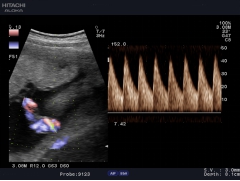

自動IMT測量

自動IMT檢測與手動測量相比提高了準確性,更方便,分辨率為0.01mm。系統(tǒng)可以自動描記并顯示結(jié)果和直方圖,直方圖可以更加直觀的觀察病變數(shù)據(jù),為動脈硬化的準確診斷提供了更為方便的工具。